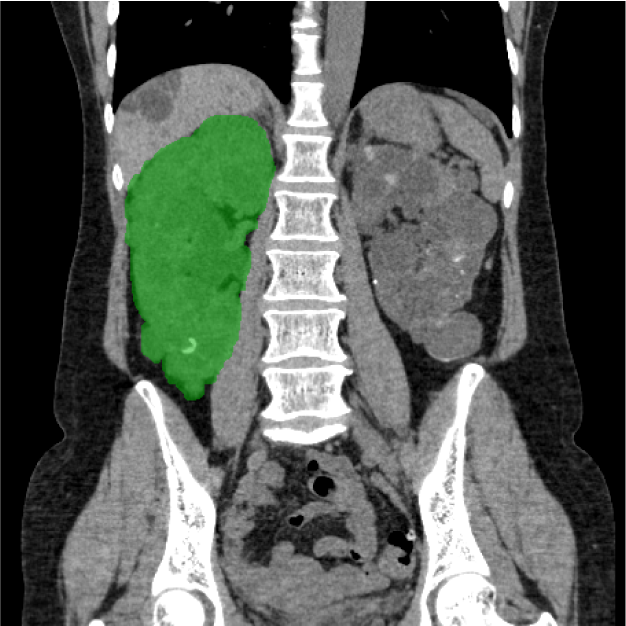

CANON(旧:東芝)社製の80列マルチスライスCTを設置し、胸部・腹部の撮影はもちろん、心臓CTや大腸CT、下肢3DCTといった専門性の高い撮影も行っています。最新のザイオワークステーションを用いて、3D画像作成、心臓解析、大腸の仮想内視鏡検査などを行っています。また、近隣の医療施設からのCT撮影依頼にも対応しており、日々たくさんご利用いただいております。被ばく線量の低減に配慮するとともに、患者さんに合った適切な線量で撮影を行うように心がけています。

心臓CT画像 大腸CT画像

腰椎CT画像 腎臓CT画像